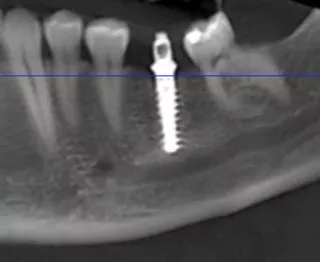

Anschließend erfolgte die Insertion des Implantates (Straumann TLX, 4.5x12 mm) mit dem Motor Implantmed (W&H) mit einer vordefinierten Eindrehkraft von 50 Ncm (Abb. 8). Die letzten 3 Gewindegänge wurden mit der Handratsche eingedreht, um die notwendige Primärstabilität mit hoher händischer Taktilität zu prüfen (Abb. 9). Die vertikale Implantatposition wurde so gewählt, dass der aufgeraute Titananteil epikrestal abschließt (Abb. 10, 11). Der maschinierte Anteil des Tissue Level Implantates ergibt somit einen Abschluss auf Gingivaniveau, wodurch eine Verschiebung der Anschlussstelle für die Prothetik weg vom ossären Niveau erfolgt und die biologische Breite sicher eingehalten werden kann. Die Primärstabilität des Implantates lag bei 50 Ncm. Eine Einheilkappe wurde aufgebracht (Bild 18) und der Wundverschluss mit nicht resorbierbarer Naht der Stärke 5-0 durchgeführt. Für einen exakten und stabilen Wundverschluss wurde der vestibuläre Weichgewebelappen kragenförmig moduliert und in Double-Sling-Technik adaptiert (Abb. 12). Das postoperative Röntgenbild zeigt die korrekte Position des Implantates mit ausreichend apikalem Abstand zum Verlauf des Nervus alveolaris inferior (Abb. 13).

Abb. 18: Röntgenkontrolle sechs Monate nach Insertion mit hervorragender Osseointegration unter Belastung.